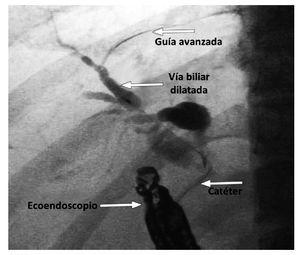

¿ Figura 2. Colangiograma luego de acceder al colédoco, por punción duodenal.

¿ Figura 4. Colédoco dilatado por cáncer de páncreas, sin flujo al dopler A). Punción del colédoco B). Colangiograma C). Paso de la prótesis transduodenal D). Drenaje biliar con total pasage de prótesis transduodenal E). Visión endoscópica de prótesis F).